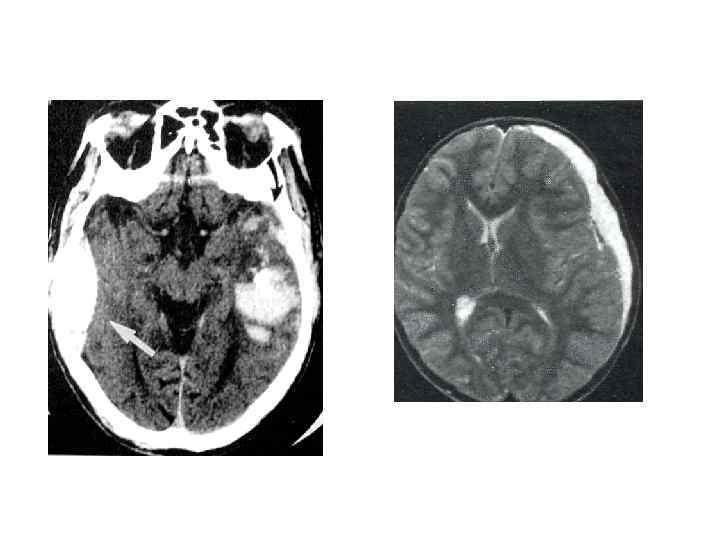

03. 72. Клиника прорыва гематомы в желудочки мозга характеризуется признаками: 1. кома-сопор 2. гипертермия 3. горметония 4. двусторонние патологические знаки 5. расстройства витальных функци _______

диагноз